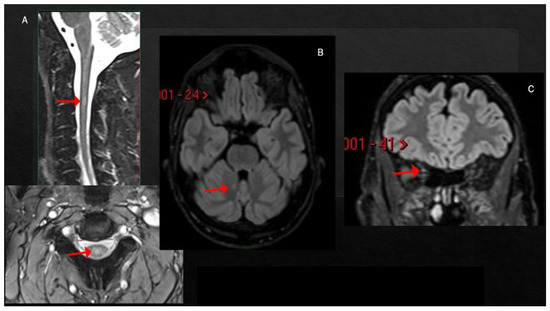

3. MS Relapses after COVID-19 Infection